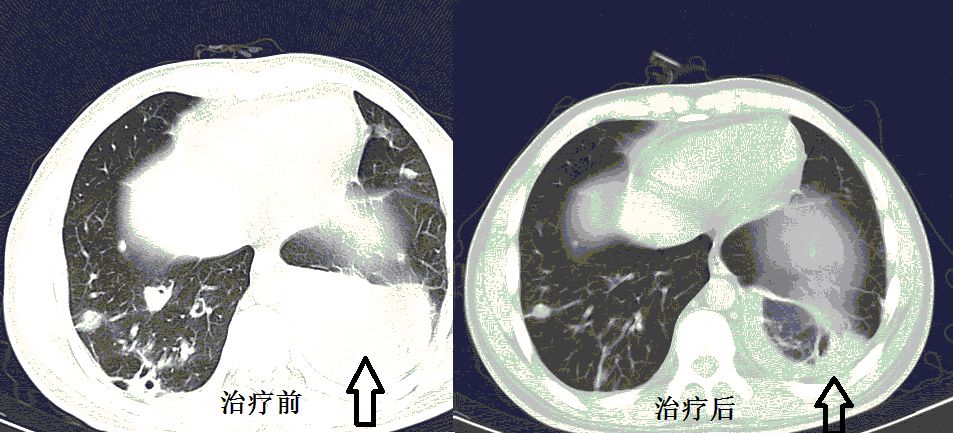

肺炎克雷伯杆菌,是肺炎常见细菌,典型的影像学表现是叶间裂下坠。什么是叶间裂下坠?书上只有文字,我也可以意会到,然而画面很模糊。多年以后,我才突然秒懂!

叶间裂下坠,从CT上看,就感染的肺组织膨胀了!

肺炎克雷伯杆菌,就是这么骄傲的细菌,非常喜欢自我膨胀!控制不住的自我膨胀!

最后,再来回望一下,什么是叶间裂下坠。

肺炎克雷伯杆菌,你就膨胀吧!